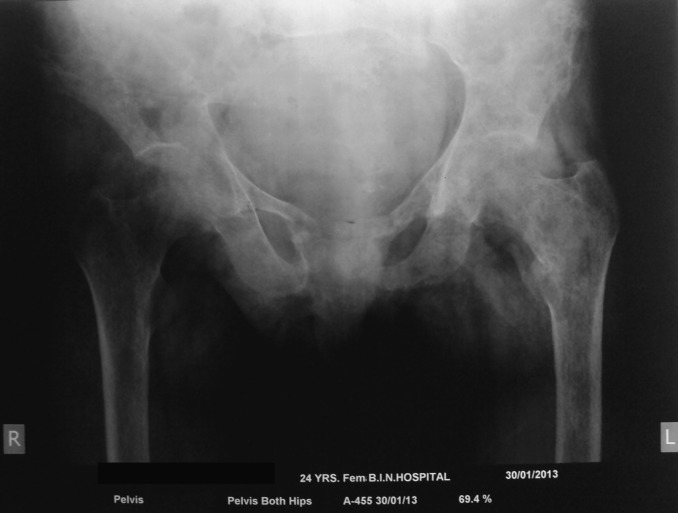

Unlabelled: Parathyroid cysts are rare (0.8-3.41% of all parathyroid lesions) and usually arise secondary to cystic degeneration of parathyroid adenomas. Intrathyroidal parathyroid cysts are extremely rare with only three cases reported till date. We present a 24-year-old female with clinical and biochemical features of primary hyperparathyroidism (PHPT; Ca(2) (+): 12.1 mg/dl; intact parathyroid hormone (iPTH): 1283 pg/ml) and poor radiotracer uptake with minimal residual uptake in the left thyroid lobe at 2 and 4 h on Tc(99m) sestamibi imaging. Neck ultrasonography (USG) revealed 0.6×1 cm parathyroid posterior left lobe of thyroid along with 22×18 mm simple thyroid cyst. USG-guided fine-needle aspiration (FNA) and needle tip iPTH estimation (FNA-iPTH) from parathyroid lesion was inconclusive (114 pg/ml), necessitating FNA of thyroid cyst, which revealed high iPTH (3480 pg/ml) from the aspirate. The patient underwent a left hemithyroidectomy. A >50% drop in serum iPTH 20 min after left hemithyroidectomy (29.4 pg/ml) along with histopathology suggestive of intrathyroidal cystic parathyroid adenoma (cystic lesion lined by chief cell variant parathyroid cells without any nuclear atypia, capsular or vascular invasion surrounded by normal thyroid follicles) confirmed that the parathyroid cyst was responsible for PHPT. This report highlights the importance of FNA-iPTH in localizing and differentiating a functional parathyroid lesion from nonfunctional tissue in PHPT.

Learning points: Fine-needle aspiration from suspected parathyroid lesion and needle tip iPTH (FNA-iPTH) estimation from the saline washing has an important role in localizing primary hyperparathyroidism (PHPT).FNA-iPTH estimation may help in differentiating functional from nonfunctional parathyroid lesion responsible for PHPT.iPTH estimation from aspirate of an intrathyroid cyst is helpful in differentiating intrathyroidal parathyroid cyst from thyroid cyst.